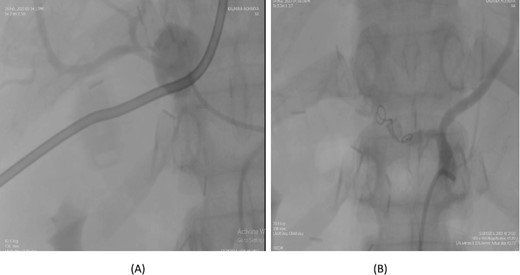

A 36-year-old female underwent a Whipple’s pancreaticoduodenectomy for pancreatic adenocarcinoma. On the fifth postoperative day, she experienced massive upper gastrointestinal bleeding, confirmed by endoscopy showing massive clots. A contrast-enhanced CT angiogram revealed a pseudoaneurysm from the proper hepatic artery, with abrupt truncation of the left gastric artery. Angioembolization was performed, with coil embolization of the proper hepatic artery and super selective embolization of the left gastric artery using gel foam. However, 32 days later, the patient experienced re-bleeding. A follow-up CT angiogram showed dislodging of the coil in the proper hepatic artery, allowing contrast through the coil and into the pseudoaneurysm. A second angioembolization repositioned the coil and used 70% glue and Lipiodol for embolization. Post-procedure, the patient had no further complications and was stable at follow-up (Fig. 3).

Case 3. (A) Angiogram shows pseudoaneurysm from proper hepatic artery. (B) Angioembolization of proper hepatic artery with coil.